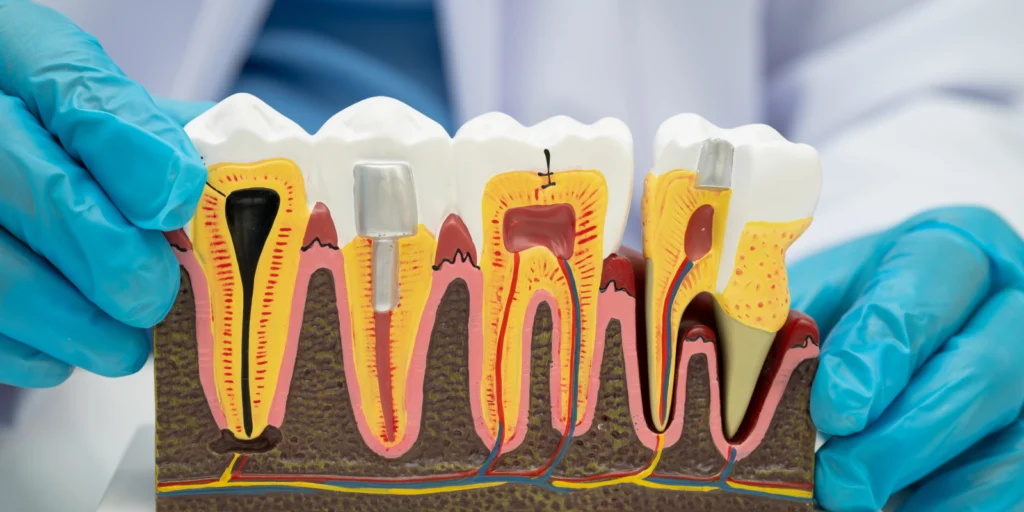

L’endodontie est la spécialité dentaire qui traite les tissus internes de la dent, appelés pulpe dentaire. La pulpe se trouve au centre de chaque dent et contient des nerfs, des vaisseaux sanguins et des tissus mous. Lorsque cette pulpe est infectée ou endommagée, elle doit être traitée pour éviter l’extraction de la dent. Ce traitement peut inclure la dévitalisation (ou traitement de canal) et le retraitement endodontique si le traitement initial échoue.

Une dévitalisation (aussi appelée traitement de canal) est une procédure dentaire qui consiste à retirer la pulpe dentaire, c’est-à-dire le tissu mou situé au centre de la dent, qui contient des nerfs et des vaisseaux sanguins. Cette intervention est réalisée lorsque la pulpe est infectée ou endommagée, généralement à cause de caries profondes, de traumatismes ou d’infections bactériennes.

Le traitement de canal, ou dévitalisation, consiste à retirer la pulpe infectée, à nettoyer les canaux de la dent, puis à les remplir pour éviter toute nouvelle infection.

Une fois que les canaux sont nettoyés, le docteur les remplit avec un matériau de scellement appelé gutta-percha. Ce matériau permet de sceller les canaux et d’éviter que des bactéries ne se développent à nouveau à l’intérieur.

Le dentiste restaure la dent en la scellant avec une obturation permanente. Dans certains cas, une couronne est posée sur la dent pour renforcer sa structure et garantir sa durabilité et son apparence esthétique.